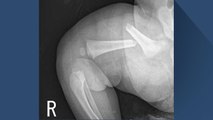

지금 보고 계시는 이 엑스레이 사진.

생후 50일 된 여자아기의 허벅지 뼈가 완전히 부러진 모습인데요.

사진으로만 봐도 말 못하는 아기가 얼마나 고통스러웠을지 짐작이 갑니다.

허벅지 뼈뿐만 아니라 쇄골도 부러진 이 아기, 무슨 사고라도 당한 걸까요?